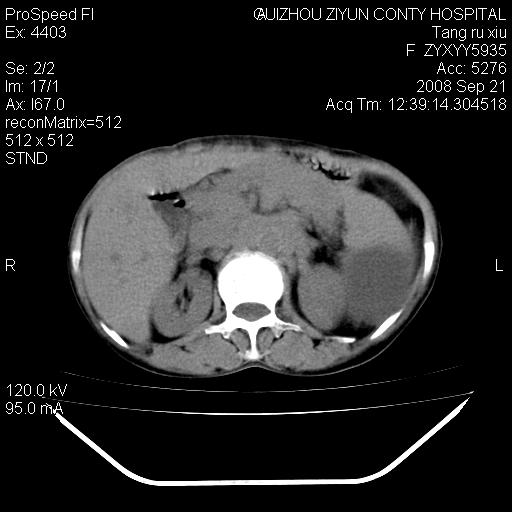

f、57岁,上腹痛.2月,近来胸闷。2月前在外院摄胸片示左侧胸腔少量积液。

(患者腹痛入院,欲吐,临床医生说禁饮,所以没有口服对比剂)

肝脏大小形态尚可,其实质内可见多发大小不等的低密度影,边缘模糊。肝门区结构紊乱,腔静脉腹主动脉旁可见多发软组织密度影,部分融合成团块状,并向下延伸。胰腺及十二指肠结构显示不清。腹腔内脐后肠管走形僵硬,管壁可见增厚。盆腔内可见多个淋巴结影。所扫层面左侧胸腔可见大量弧形水样密度影,其内侧可见被压缩的肺组织影。左侧胸壁可见一小结节样软组织密度影,边缘模糊。心脏纵隔向右侧移位。心脏包膜内可见囊样低密度影,其内侧心房室周围可见一圈气体样密度影。纵隔内大血管旁可见多发软组织团块影,部分融合。

1.腹膜后淋巴瘤侵及肝脏,肺内及纵隔内多发转移。2.左侧大量胸腔积液并压缩性肺不张。3.心包脓肿可能,转移不除外。4.脐后局部肠管管壁增厚,考虑炎症可能,肿瘤不除外。

为什么没有人注意到腹腔脐后的那段肠管呢?那段看着很不好的样子。